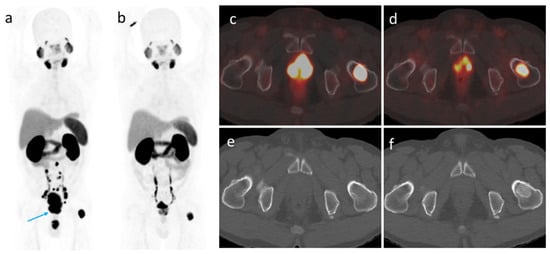

3.4. [68Ga]Ga-PSMA-11 PET/CT Imaging after ADT